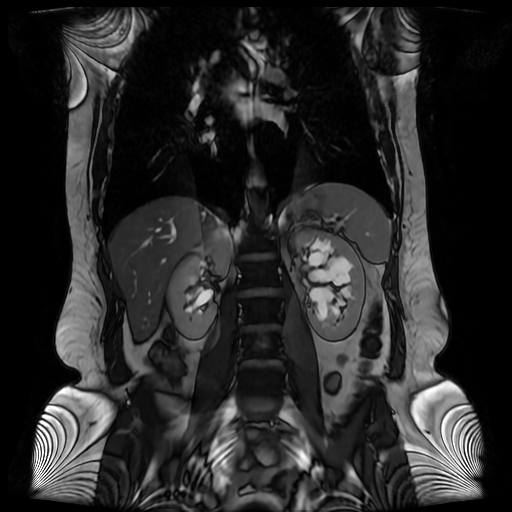

Los sistemas colectores del riñón derecho y del riñón izquierdo, muestran alteración de sus calices primarios y secundarios, mostrando dilatación, la pelvis renal y el uréter se observan de características normales lo que indica que no hay proceso obstructivo.

Se observa dilatación del sistema calicial sin proceso obstructivo compatible con una anormalidad del desarrollo de los sistemas colectores de ambos riñones, definiéndose como una “megacaliosis”